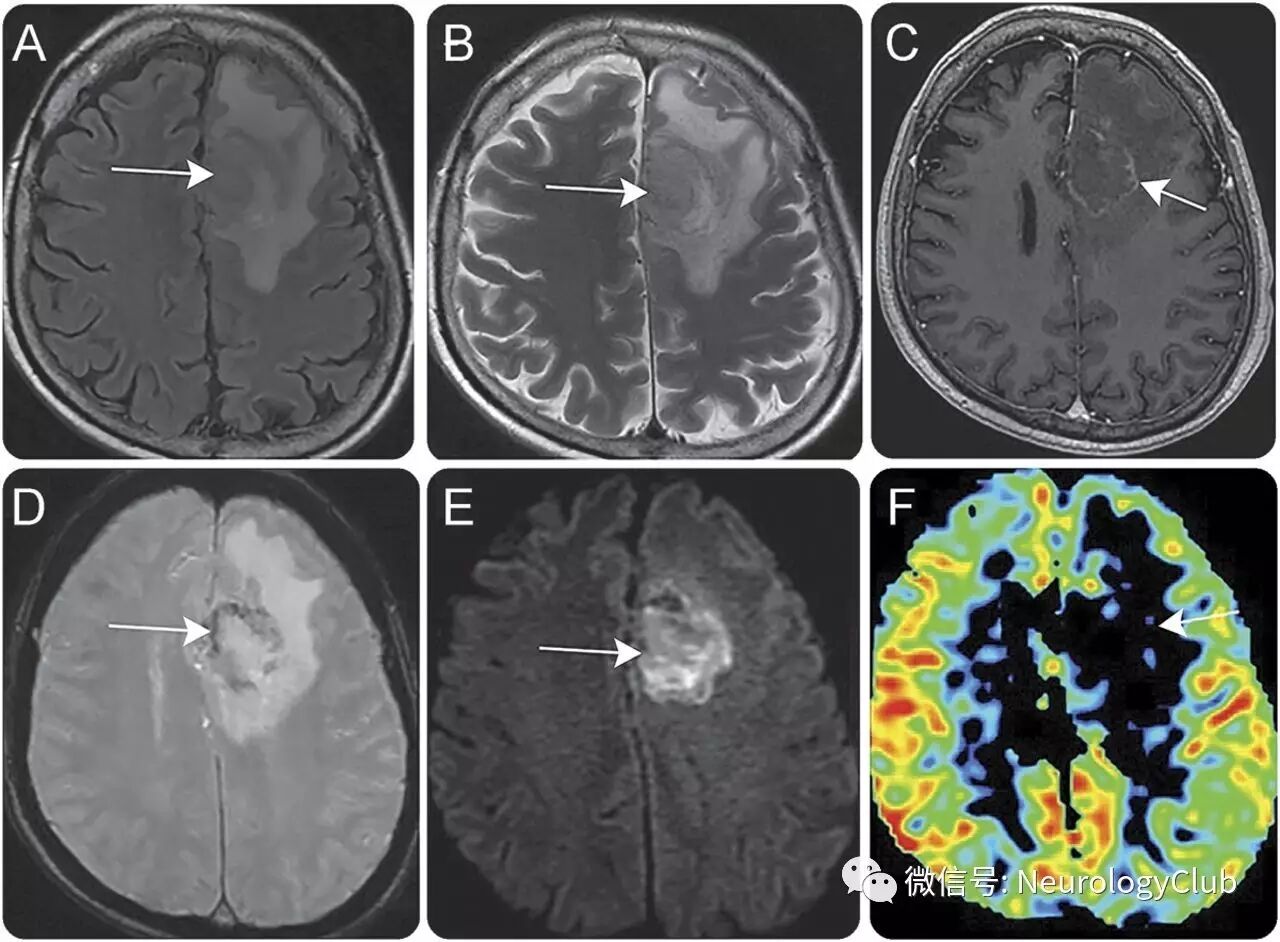

62岁男性,表现为进行性头痛和右侧肢体无力7天。患者在16年前因糖尿病肾病接受肾移植。术后长期服用强的松和麦考酚酸酯。查体提示右侧轻偏瘫。头颅MRI可见左侧额叶占位性病变(图1)。血液学检查结果无殊。

(图1:FLAIR[A]和T2WI[B]可见左侧额叶较大的脑内肿块[箭];T1增强[C]可见明显的周围强化[箭];磁敏感加权成像[D]提示病灶内出血[箭];DWI[E]和对应的ADC[未放图]证实弥散受限[箭];怀疑脑肿瘤,但动脉自旋标记灌注成像[F]提示低灌注[箭])